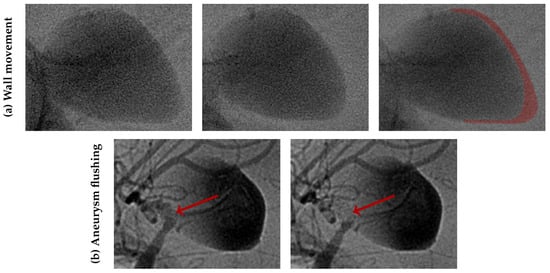

- Zhou, J.; Guo, Q.; Chen, Y.; Lin, B.; Ding, S.; Zhao, H.; Pan, Y.; Wan, J.; Zhao, B. Irregular Pulsation of Intracranial Aneurysm Detected by Four-Dimensional CT Angiography and Associated with Small Aneurysm Rupture: A Single-Center Prospective Analysis. Front. Neurol. 2022, 13, 1–9. [Google Scholar] [CrossRef]

- Vanrossomme, A.; Eker, O.; Thiran, J.P.; Courbebaisse, G.; Zouaoui Boudjeltia, K. Intracranial Aneurysms: Wall Motion Analysis for Prediction of Rupture. Am. J. Neuroradiol. 2015, 36, 1796–1802. [Google Scholar] [CrossRef] [PubMed]

- Stam, L.B.; Aquarius, R.; de Jong, G.A.; Slump, C.H.; Meijer, F.J.; Boogaarts, H.D. A review on imaging techniques and quantitative measurements for dynamic imaging of cerebral aneurysm pulsations. Sci. Rep. 2021, 11, 2175. [Google Scholar] [CrossRef]